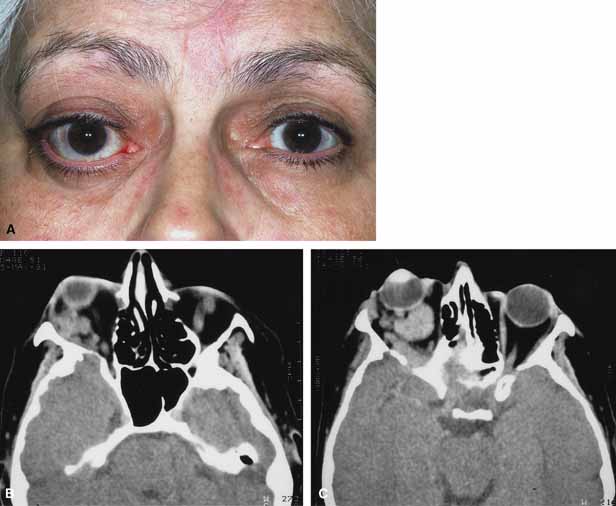

In some patients the orbitopathy is more aggressive and rapidly evolving with acute proptosis over 1 to 2 days, swelling of the lids and conjunctiva, diplopia, corneal exposure, and optic neuropathy (Fig. 6A). This presentation may be confused with disorders such as nonspecific orbital inflammation or carotid-cavernous fistula.44 The differential diagnosis of acute proptosis with enlarged extraocular muscles includes thyroid orbitopathy, vascular causes (arteriovenous fistulas), inflammation (orbital myositis, sarcoid), infection, primary invasive tumor, metastasis to the extraocular muscles.45,46

Fig. 6 A. A 56-year-old female presented with a 2-day history of proptosis, lid swelling, conjunctival chemosis/injection, and double vision. Thyrotropin (TSH) level was extremely low and a computed tomography (CT) scan revealed grossly enlarged extraocular muscles. A diagnosis of acute thyroid eye disease was made. B. Axial computed tomographt (CT) scan illustrating diffuse enlarged extraocular muscles characteristic of thyroid eye disease. C. Coronal computed tomography (CT) scan showing enlargement of extraocular muscles.

CT classically reveals enlarged extraocular muscles (Fig. 6B and 6C). One or all of the muscles may be involved and there is bilateral involvement in the majority. The most frequently involved muscle is the inferior rectus followed by the medial, superior, and lateral rectus (opposite to the spiral of Tillaux).40 The tendons of the affected recti muscles are typically not thickened, resulting in a characteristic fusiform enlargement of the muscle, whereas in myositis secondary to nonspecific orbital inflammation the tendons are generally thickened. Other signs are also useful to distinguish between the two. Bilaterally is unusual in myositis but common with thyroid. Thyroid usually has several muscles involved while myositis more often only has one muscle involved. In myositis the muscle border is more likely to be irregular or fuzzy with or without involvement of adjacent fat whereas in thyroid disease the muscle border is regular and there is no fat involved. Clinically there are also several distinguishing features. Myositis classically presents more rapidly and is associated with pain on extraocular movement. This is rare with thyroid eye disease. The eyelid signs (retraction, flare) are common with thyroid but absent in myositis.